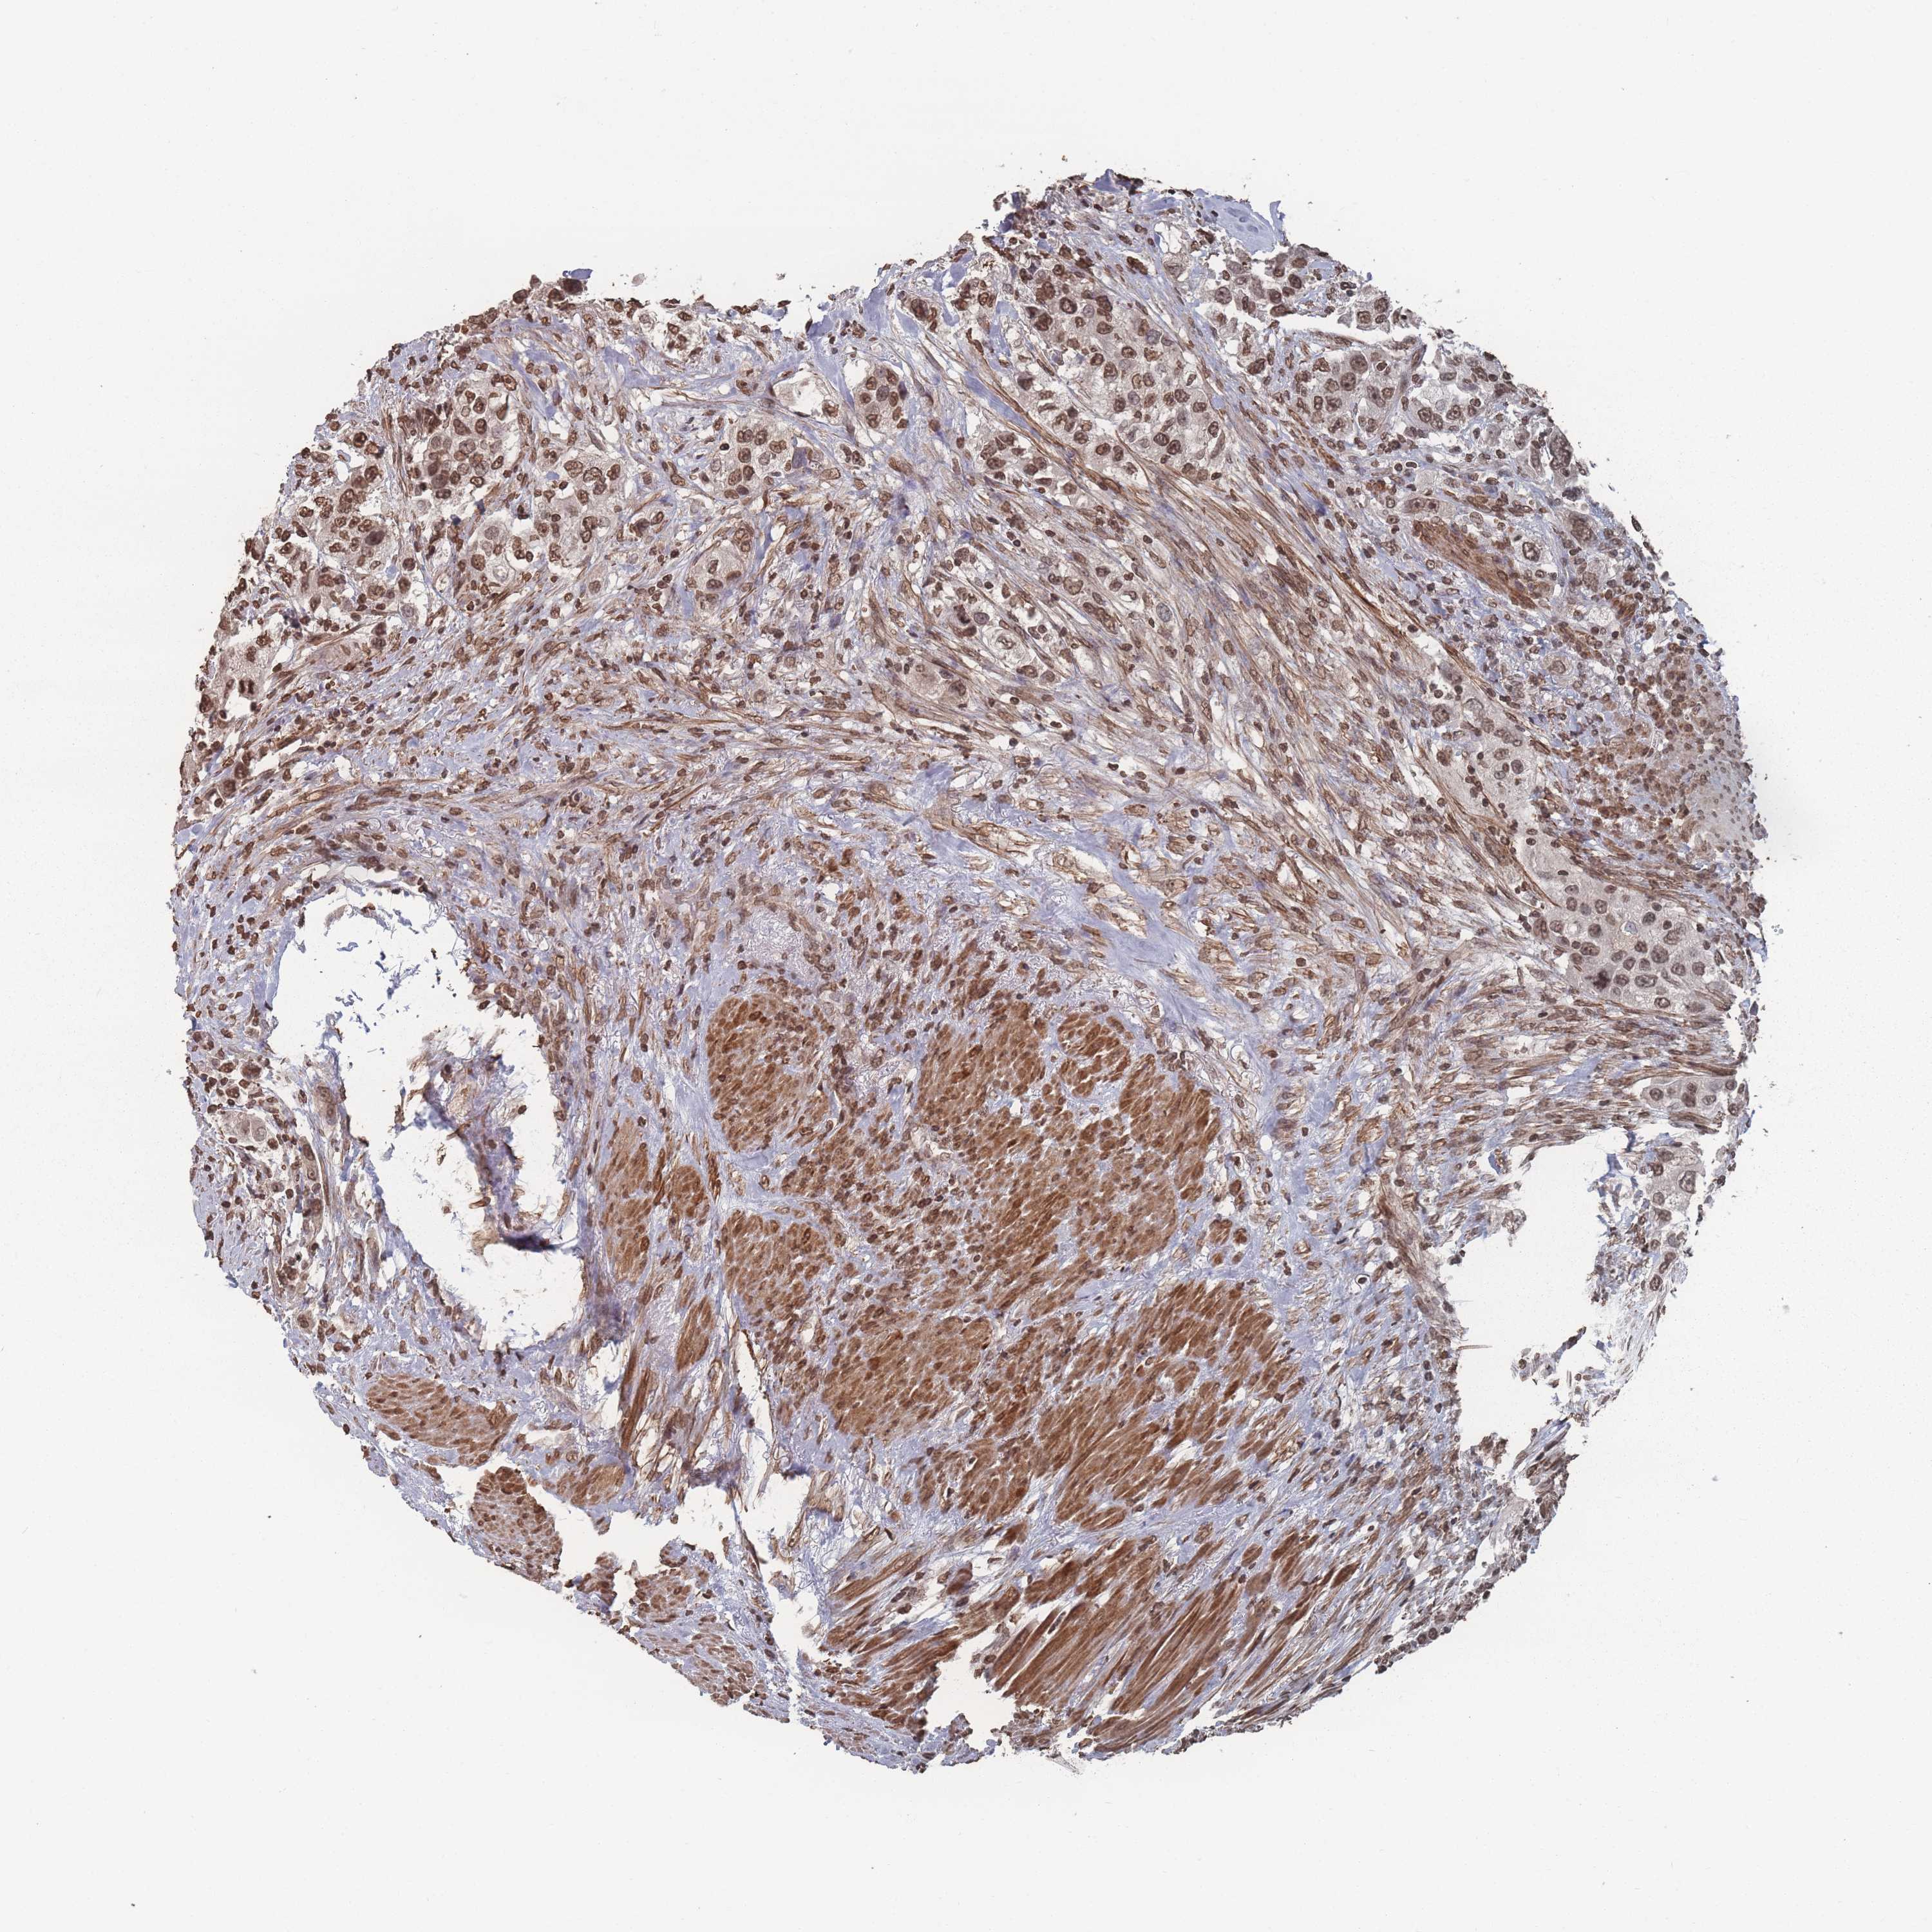

UROTHELIAL CANCER - Protein expressioni

A mouse-over function shows sample information and annotation data. Click on an image to view it in a full screen mode. Samples can be filtered based on level of antibody staining by selecting one or several of the following categories: high, medium, low and not detected. The assay and annotation is described here.

Antibody stainingi

Antibody staining in the annotated cell types in the current human tissue is reported as not detected, low, medium, or high, based on conventional immunohistochemistry profiling in selected tissues. This score is based on the combination of the staining intensity and fraction of stained cells.

Each image is clickable and will lead to virtual microscopy that enables deeper exploration of all samples and also displays staining intensity scores, fraction scores and subcellular localization as well as patient and tissue information for each sample.

Antibody HPA049570

Staining

High

Medium

Low

Not detected

Intensity

Strong

Moderate

Weak

Negative

Quantity

>75%

75%-25%

<25%

None

Location

Nuclear

Cytoplasmic/membranous

Cytoplasmic/membranous,nuclear

Urothelial carcinoma, Low grade

Urothelial carcinoma, High grade